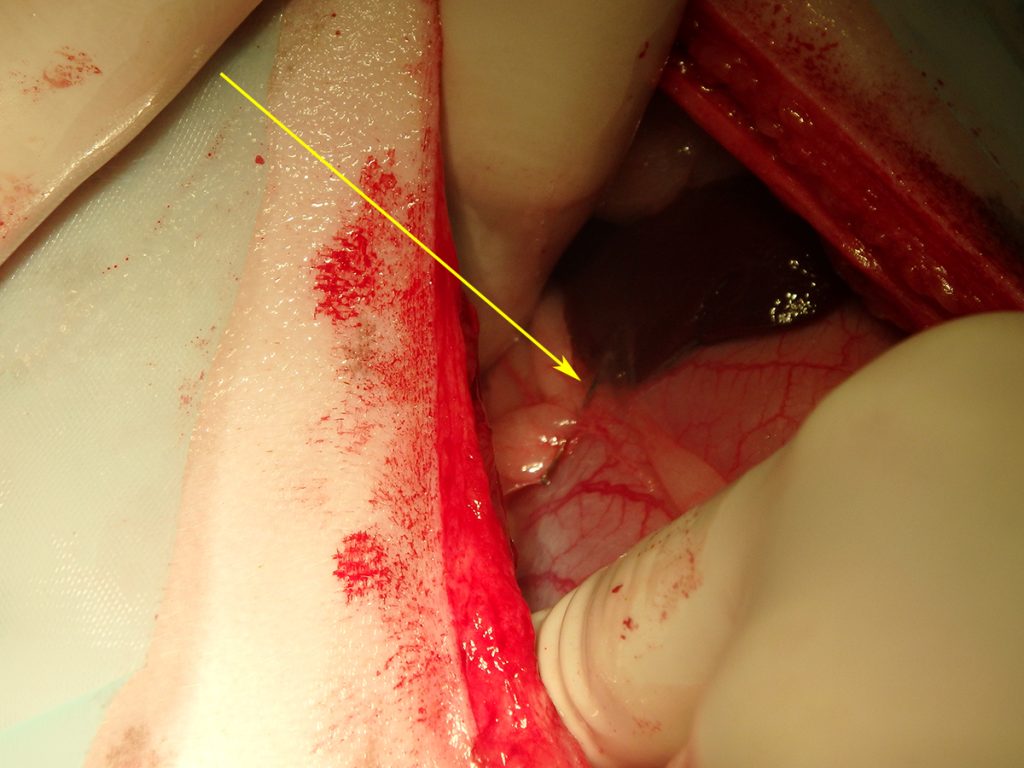

Na het openen van de buik en het verwijderen van wat vet, is de chirurg gaan zoeken. Al snel vindt hij aan de voorzijde van de maag een vreemd vliesje. Dit blijkt een stukje vet en vlies te zijn, wat op het oogje van de naald verkleefd zat. Ruim 2/3 van de naald blijkt in een leverlob te zitten. De naald blijkt er niet eenvoudig uitgetrokken te kunnen worden. Hij zit aardig vast. Dit suggereert dat hij er misschien al iets langer zit. Bij het verwijderen van de naald ontstaat er een klein scheurtje in de lever. De bloeding kan worden gestelpt met een speciaal matje dat stolling bevordert. Hierna is het een kwestie van de buik sluiten en Lady mag weer wakker worden.